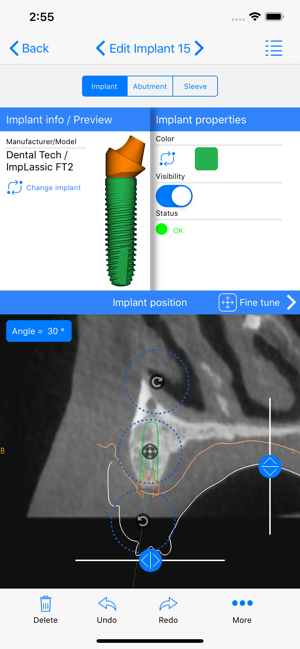

ICX-Magellan X is a cloud-based Software concept used for CBCT-Analysis and to create Implant-Treatment plans.

The ICX-Magellan X App completes this System primarily regarding communication, treatment-plans that were prepared at the pc can be shared with other users in real-time, commented, changed or confirmed.

The App can be integrated supporting any workflow; existing treatment-plans can be recalled, edited or used for patient-education anywhere anytime.